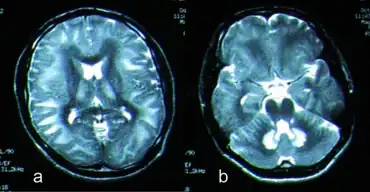

Due to advances in MRI, this neurological disorder has been characterized more successfully in more recent years. MRI can aid in the detection of injured brain tissue; however, the severity and extent of the damage demonstrated by imaging does not always reflect patient clinical status.[8] Toxic leukoencephalopathy encompasses the degeneration of white matter tracts devoted to higher cerebral function;[2] however, white matter can appear normal until the disease has progressed more intensely.[1] Toxic leukoencephalopathy-related damage to central nervous system (CNS) white matter, typically of the periventricular nucleus, and other structures in the brain is often bilateral and symmetric. Heroin-induced leukoencephalopathy often involves damage to cerebellar white matter, posterior cerebral white matter, posterior limb of internal capsule, and cerebellar peduncles.[1] The occipital lobe is typically most affected though the frontal, parietal, and temporal lobes have shown involvement as well. Other toxins have been shown to extend damage to other structures of the brain, including the hippocampus, dorsal medulla, and brainstem.[8]